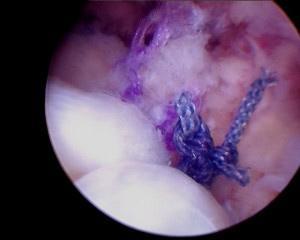

Sutures placed in tendon

Rotator cuff repaired